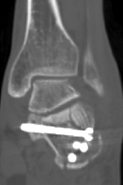

常规切开复位内固定术创伤大、复位不准确,存在慢性疼痛、皮肤坏死、足踝活动受限、创伤性关节炎等风险。于是,骨科在中心主任吴超带领下,采用第三代天玑骨科手术机器人为程某开展跟骨微创内固定手术,该手术时间短、透视少、实现了精准复位和螺钉固定;术后影像显示螺钉位置良好,患者关节面恢复。

术后影像显示螺钉位置良好